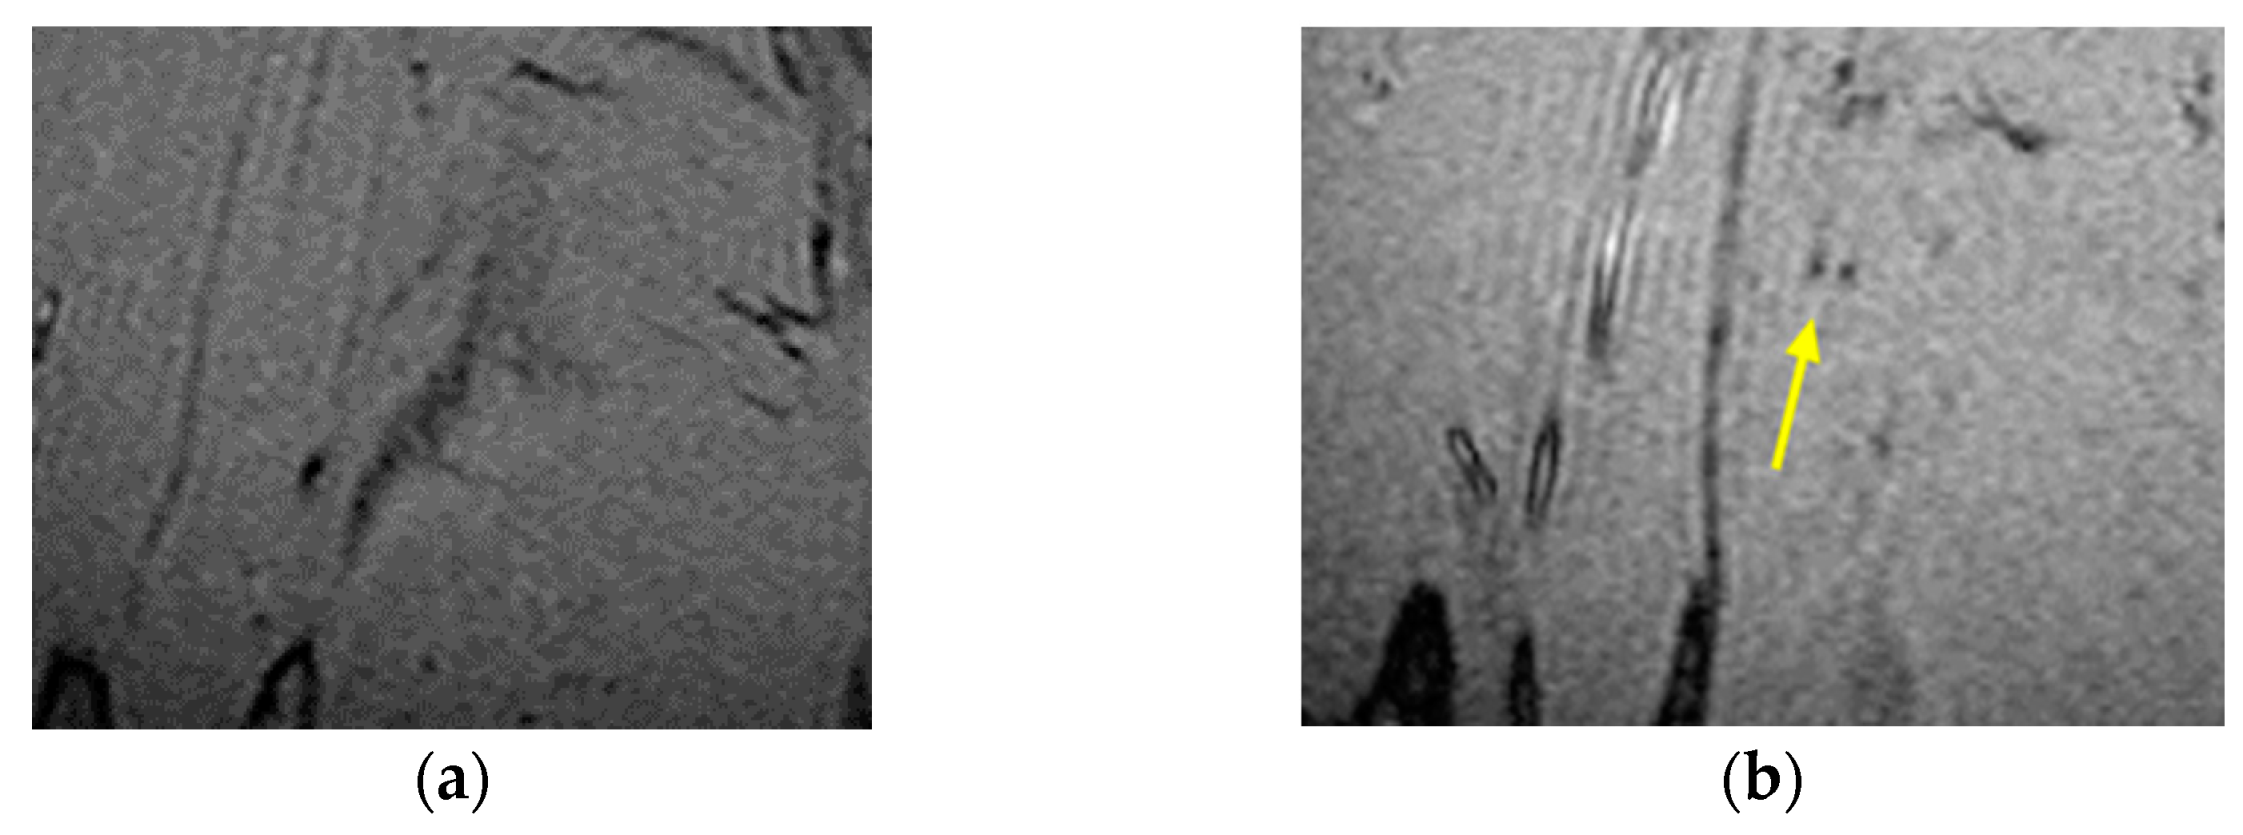

The technique was tested on a series of MRI images of the leg comprising nanoparticles using the MATLAB and ImageJ program and applied to grayscale images of size 300 × 300 pixels. The format used was (.tiff). The first set of data contained a stack of 50 images of a mouse calf with IO-NPs and a second set of 50 images of identical sizes, but no IO-NPs. The aim was to calibrate and validate the consistency of the IO-NP identification method. Figure 1 shows the two slices with and without IO-NPs.

Figure 1.

MR images of the mouse calf region (a) lacking IO-NPs and (b) with IO-NPs, as black dots in the image pointed by yellow arrow.